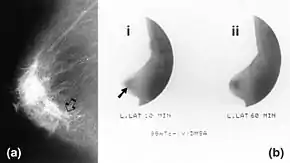

![]() Mammography (left) and DMSA scintimammography (right) images of 4.5cm breast carcinoma | |

Molecular breast imaging (MBI), also known as scintimammography, is a type of breast imaging test that is used to detect cancer cells in breast tissue of individuals who have had abnormal mammograms, especially for those who have dense breast tissue, post-operative scar tissue or breast implants.[1]